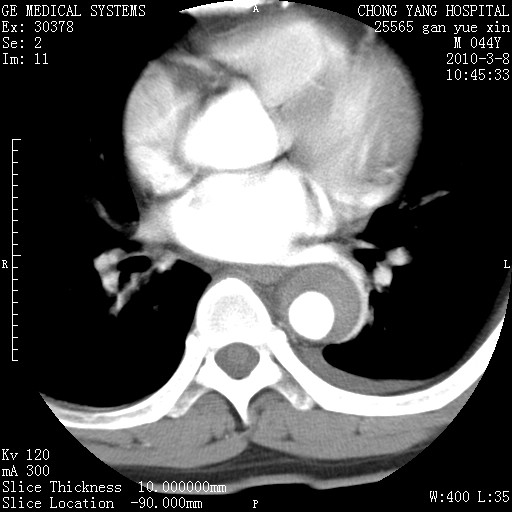

标题: CT24940:主动脉增强,典型病例。 [打印本页]

标题: CT24940:主动脉增强,典型病例。

夹层动脉瘤。

动脉夹层

夹层动脉瘤,典型

主动脉夹层。

动脉夹层的分型:

⒈debakey分型:根据主动脉夹层累及部位,分为三型:ⅰ型:原发破口位于升主动脉或主动脉弓部,夹层累及升主动脉、主动脉弓部、胸主动脉、腹主动脉大部或全部,少数可累及髂动脉。ⅱ型:原发破口位于升主动脉,夹层累及升主动脉,少数可累及部分主动脉弓。ⅲ型:原发破口位于左锁骨下动脉开口远端,根据夹层累及范围又分为ⅲa,ⅲb。ⅲa型:夹层累及胸主动脉。ⅲb型:夹层累及升主动脉、腹主动脉大部或全部。少数可累及髂动脉。

⒉stanford分型:a型:夹层累及升主动脉,无论远端范围如何。b型:夹层累及左锁骨下动脉开口以远的降主动脉。

夹层动脉瘤,少量胸水

夹层动脉瘤;左侧少量胸腔积液。

典型主动脉夹层。